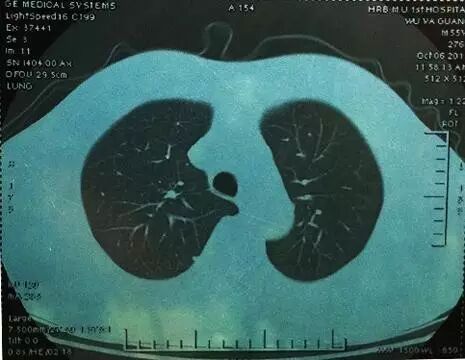

是指肺内直径≤3cm的密度增高影,通俗讲就是CT上黑色的肺里有小白点。>3cm的白色块状影称为肺肿块,通常肿瘤的可能性很大。

结节直径≤3cm

结节直径>3cm